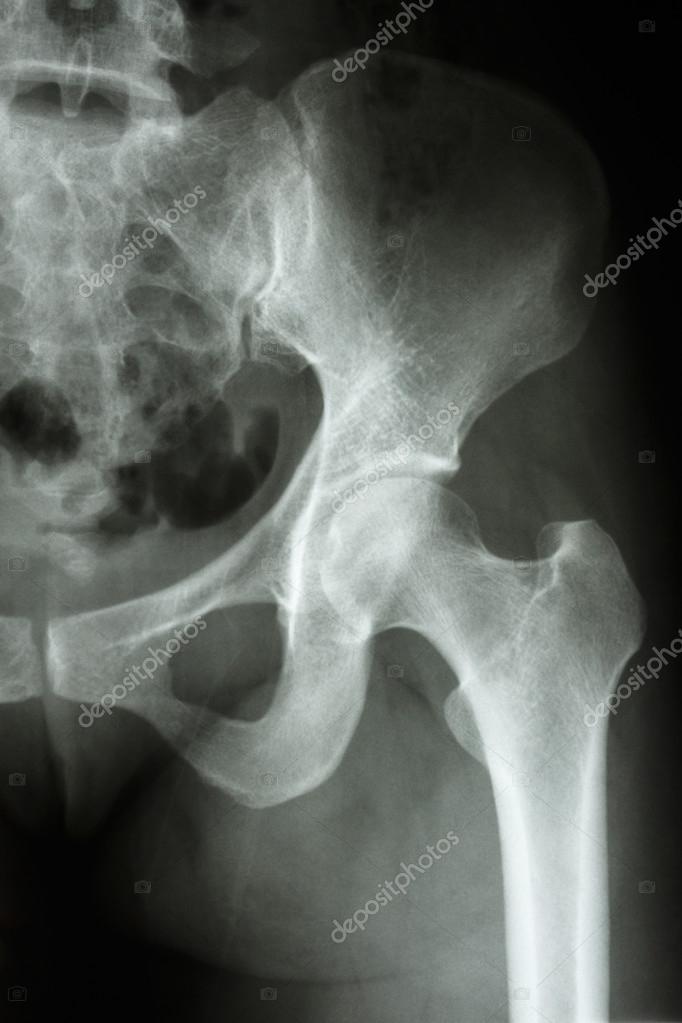

Вертлужная впадина-это глубокая чашевидная структура, которая охватывает головку бедренной кости в тазобедренном суставе (рис . 9 .4) .

Кости грудной клетки - Подгрудинный угол . Кости черепа - Мозжечковая ямка . Вертлужная впадина . , acetabulum . Формируется подвздошной, лобковой и седалищной костями .

Перелом вертлужной впадины - это нарушение целостности таза в области суставной ямки тазобедренного сустава . Может сочетаться с вывихом тазобедренного сустава и переломом . . .

По данному снимку возможно заподозрить перелом левой вертлужной впадины, поскольку Также с помощью прицельного снимка определена целостность контуров запирательного . . .